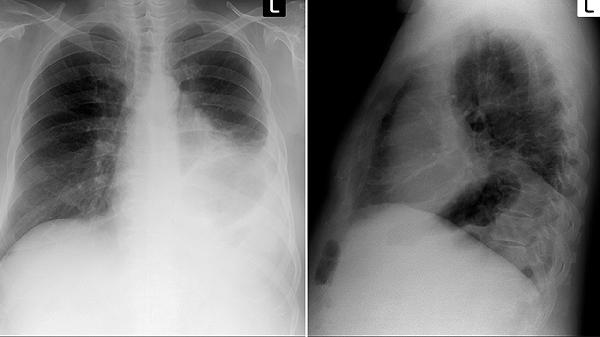

四、黄金筛查法则

建议40岁以上人群,每年做一次低剂量螺旋CT检查。如果出现上述症状,别犹豫,尽快去呼吸科做喉镜+影像学检查。记住:早期发现的治疗几率能达到80%以上,而晚期五年生存率不足20%。